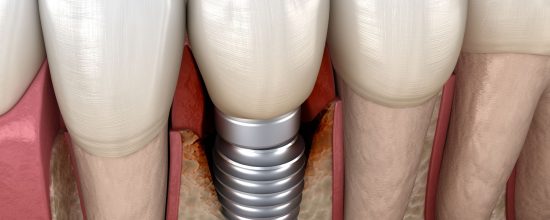

Los implantes dentales son un método muy seguro y con muchas garantías para solucionar la caída de una pieza dental y con ello salvaguardar la estabilidad de los dientes colindantes y de la estructura ósea de la zona. Aunque, muy de vez en cuando y por distintas causas, estos pueden tener complicaciones.

La periimplantitis es la inflamación de las encías que rodean a un implante dental. Esta situación, al igual que una periodontitis normal, pone en peligro el hueso que hace de soporte para la pieza implantada.